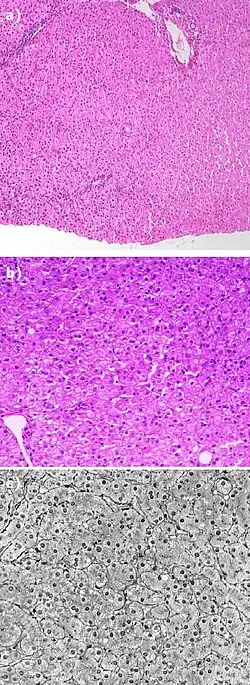

Although the revision was helpful in some ways, it also had consequences because this new compound was not exactly like the original. Due to the methyl/ethyl group added to the compound, liver stain was found as a result of the transformation. In addition, all of the carbon-17 added compound was effected, and caused chemical damages to the liver.(source needed)